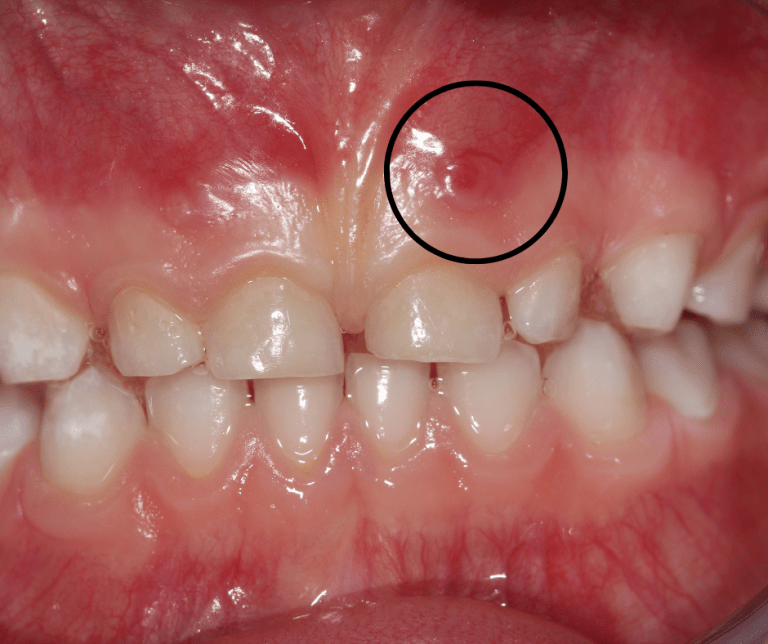

Any thoughts on this white bump on upper gum? Mostly painless, seems to

Any thoughts on this white bump on upper gum? Mostly painless, seems to Infection Gums Pimple When an infection occurs below the gum skin, it can cause an abscess to form and create a. They are usually a sign of bacterial infection due to poor oral hygiene. What’s causing this bump on my gums? A gum abscess is a pocket of pus and bacteria that forms due to an infection in the gums. It’s important to. Infection Gums Pimple.